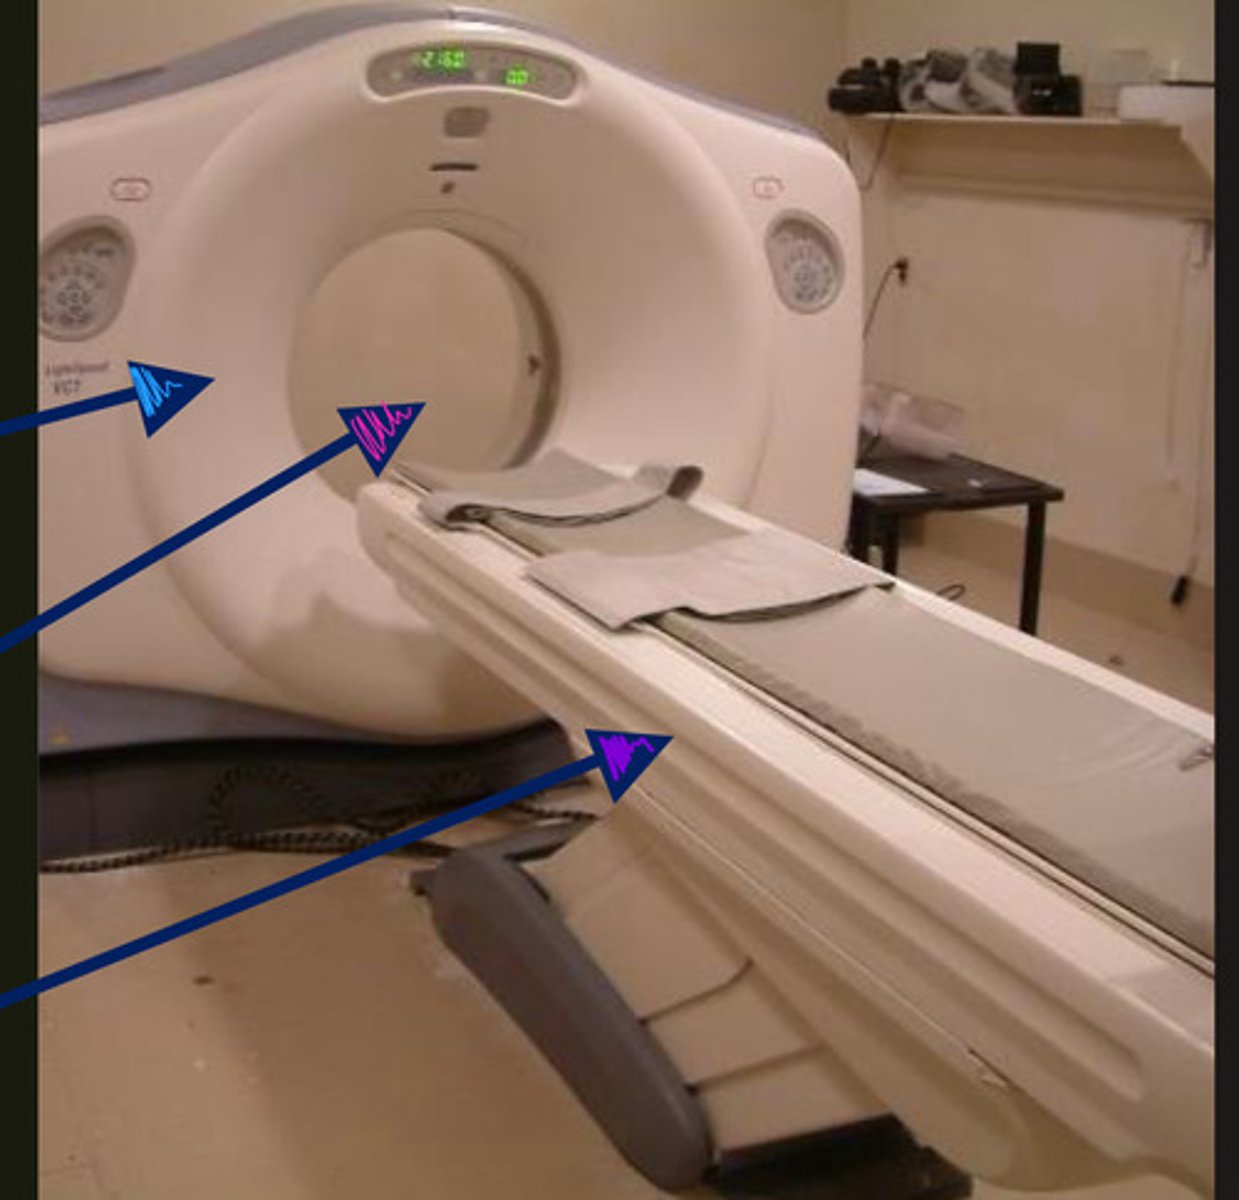

blue- gantry

pink- bore

purple- couch/table

ID parts of CT machine

x-ray tube and detectors

what two parts does the gantry of the CT machine include?

top- bore

middle- RF coil

bottom- couch/table

what are the parts of the MRI machine from top to bottom?